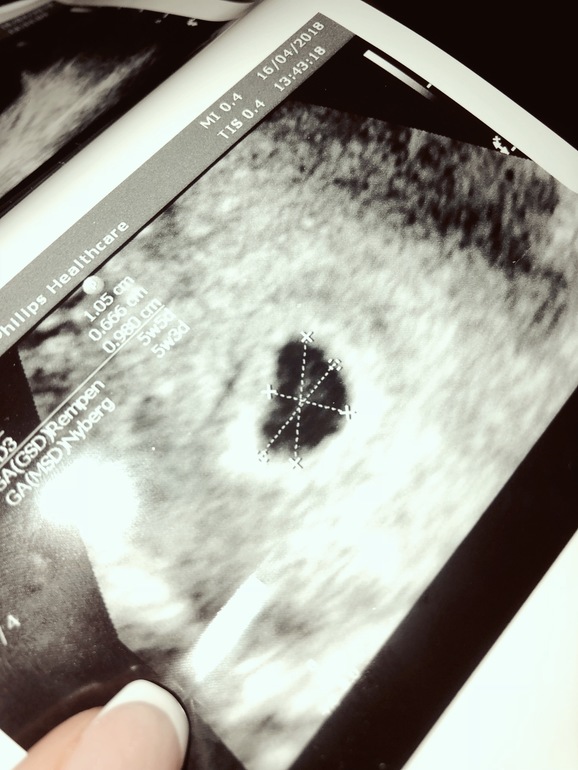

Маточная Беременность

У меня тоже месячные 8го марта последние, в пт на УЗИ ПЯ 6мм, сказали придти через 2 недели, чтобы увидеть эмбрион и сердечко, это будет 7+1

Я ходила в 6+5, все увидели. Не торопитесь, потому что могут не увидеть эмбрион или сердцебиение, придется еще раз идти.. Вы подтвердили маточную Б, что уже хорошо.

У меня в 6+3 было видно уже даже сердцебиение )

Все хорошо без сомнений)))) для эмбриончика рано, а все остальное по УЗИ супер)) вам переживать совершенно не о чем))

Я просто не понимаю по УЗИ , это ли жм и почему от него идёт ниточка ?